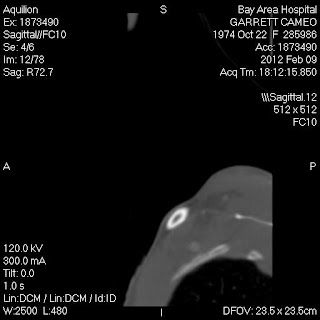

This view is of the 42nd photo in the coronal series, brain filter view. If you look right in the middle, there is a small black dot, and this is matching the same kind of result the implant in my tooth creates. The little bright circle things on my shoulders are from my hospital gown. So as you scroll down to see other views of the same photo, you will see how this artifact is picking up, and how it's near the plate in my neck, but is something separate from it. The black dot I'm referring to is in the center of the neck, a little bit higher than the R and L indicated right and left of my body, on the scan.

This is a head and neck filter, and shows the same dot. You can see a little bit of glare coming from the area, due to the metal.